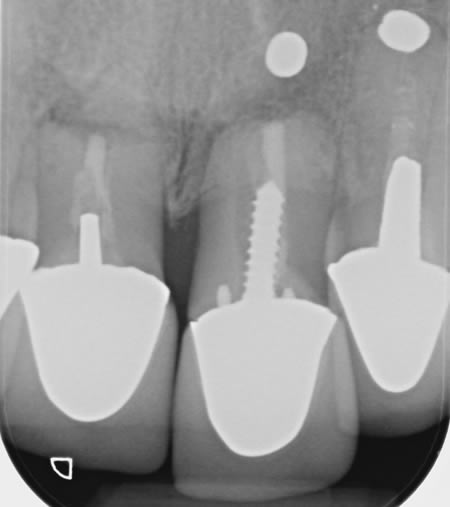

After approximately 12 months of periodontal therapy, the patient was deemed stable enough by the specialist periodontist to undergo implant treatment. An Astra EV implant was placed and a well shade matched zirconia crown was luted to an Atlantis abutment. Digital SLR pictures were used to provide the lab technician with appearance detail of the neighbouring dentition, to allow the technicians at Smile Dental Laboratory to introduce 'accents' and a realistic and seamless look to the final zirconia prosthesis.

Case H

During Treatment